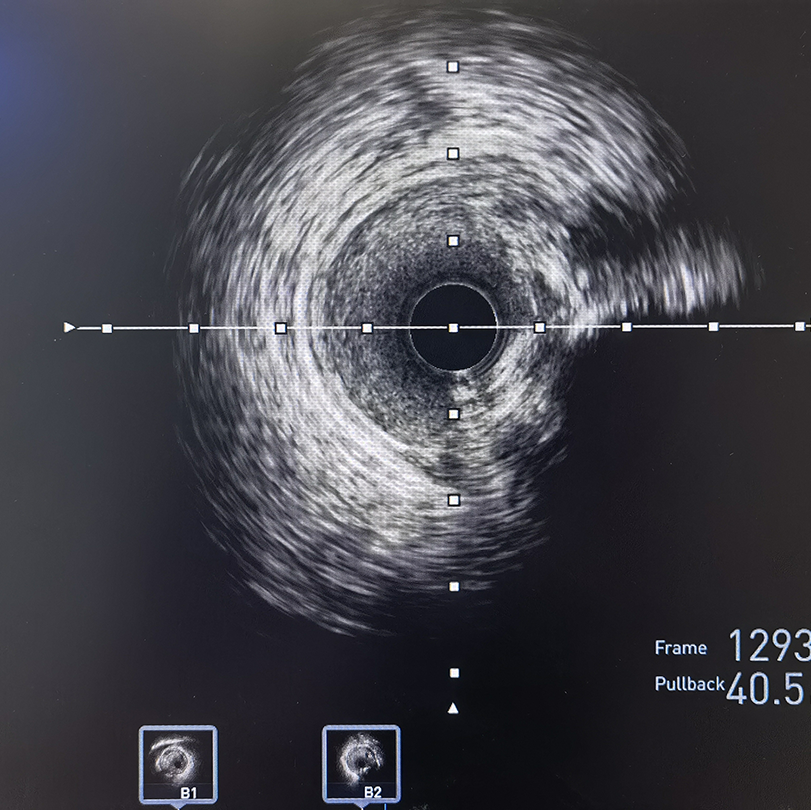

冠脉造影及IVUS检查提示前降支重度狭窄伴严重钙化

冲击波球囊是目前冠状动脉钙化病变治疗的全新技术,具有操作简单,穿孔风险低,分支可以保留导丝保护,对于残余管腔直径大的环形钙化和钙化小结都可以起到良好的斑块改良效应等优点,有望成为处理冠脉钙化的终结者;目前研究充分验证了其在处理冠脉钙化病变时的安全性和有效性。